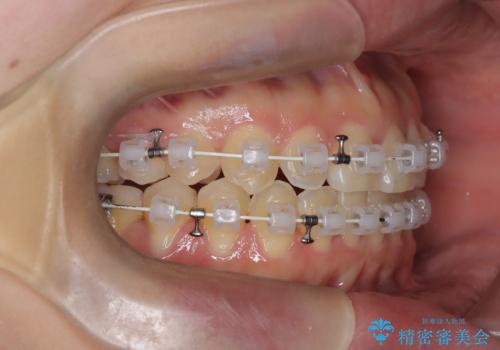

【ワイヤー矯正】一番後ろの奥歯でしか噛んでいないかみ合わせを治したい

最初は、一番後ろの奥歯でしか噛んでいない状態で、上下の前歯の先端がちょうど当たる切端咬合でした。

口腔習癖の改善及び、ワイヤー矯正にて歯列の平坦化を行うことで咬合を確立することができました。